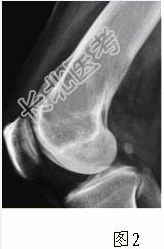

- [材料题] 患者女,35岁,左膝关节隐痛1年余,近1周加重,活动后明显疼痛。查体:左股骨下端外侧肿胀,压痛。行左膝关节正侧位CR,并行左膝关节CT扫描,见下图。

- 简答题1、根据膝关节CR和CT影像,你认为此病例的影像学表现有?

- 简答题2、对本病例,应首先考虑的诊断是?